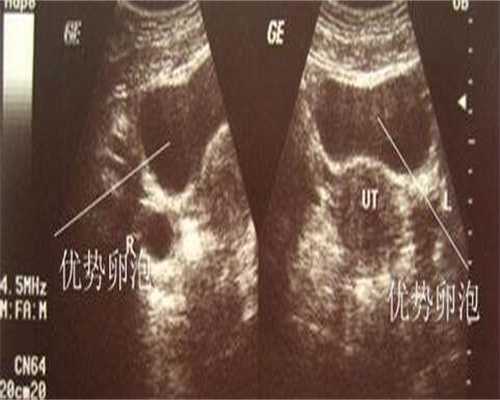

镇江供卵代生是通过代孕母亲的卵子和代孕父亲的精子结合,然后将受精卵移植至代孕母亲子宫内,让代孕母亲生下孩子的过程。这种方式一般用于不育夫妻或由于某些原因无法自然怀孕的夫妇。

在镇江,供卵代生可以选择男女性别。通过人工控制受精卵的性别,可以让父母通过代孕妈妈生出自己想要的孩子。这一过程需要医生和专业技术支持,同时也需要保证代孕妈妈和胎儿的健康。